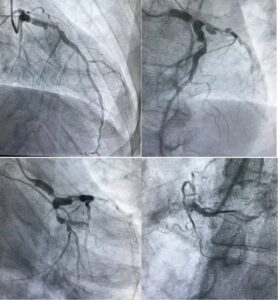

L’Hôpital de l’Amitié Sino-Guinéenne (HASIGUI), en parfaite adéquation avec la politique de développement hospitalier du Ministère de la Santé et de l’Hygiène Publique, s’inscrit pleinement dans une dynamique visant à rassurer la population guinéenne, en améliorant la qualité des soins et en renforçant son plateau technique.

Convaincu de cette vision, le Directeur Général de HASIGUI, Dr Mohamed DIANE, adopte une approche de gestion axée sur les résultats. Il œuvre avec détermination pour doter l’établissement d’un personnel soignant qualifié, compétent et profondément engagé au service des patients.

Par ailleurs, le Centre de Diagnostic de HASIGUI connaît une mutation remarquable. Il propose désormais des examens de laboratoire, d’imagerie médicale, ainsi que des analyses d’immunohistochimie de haute précision. Ces avancées majeures permettent aux médecins traitants de mieux comprendre les pathologies complexes, facilitant ainsi une prise en charge plus rapide et plus efficace.